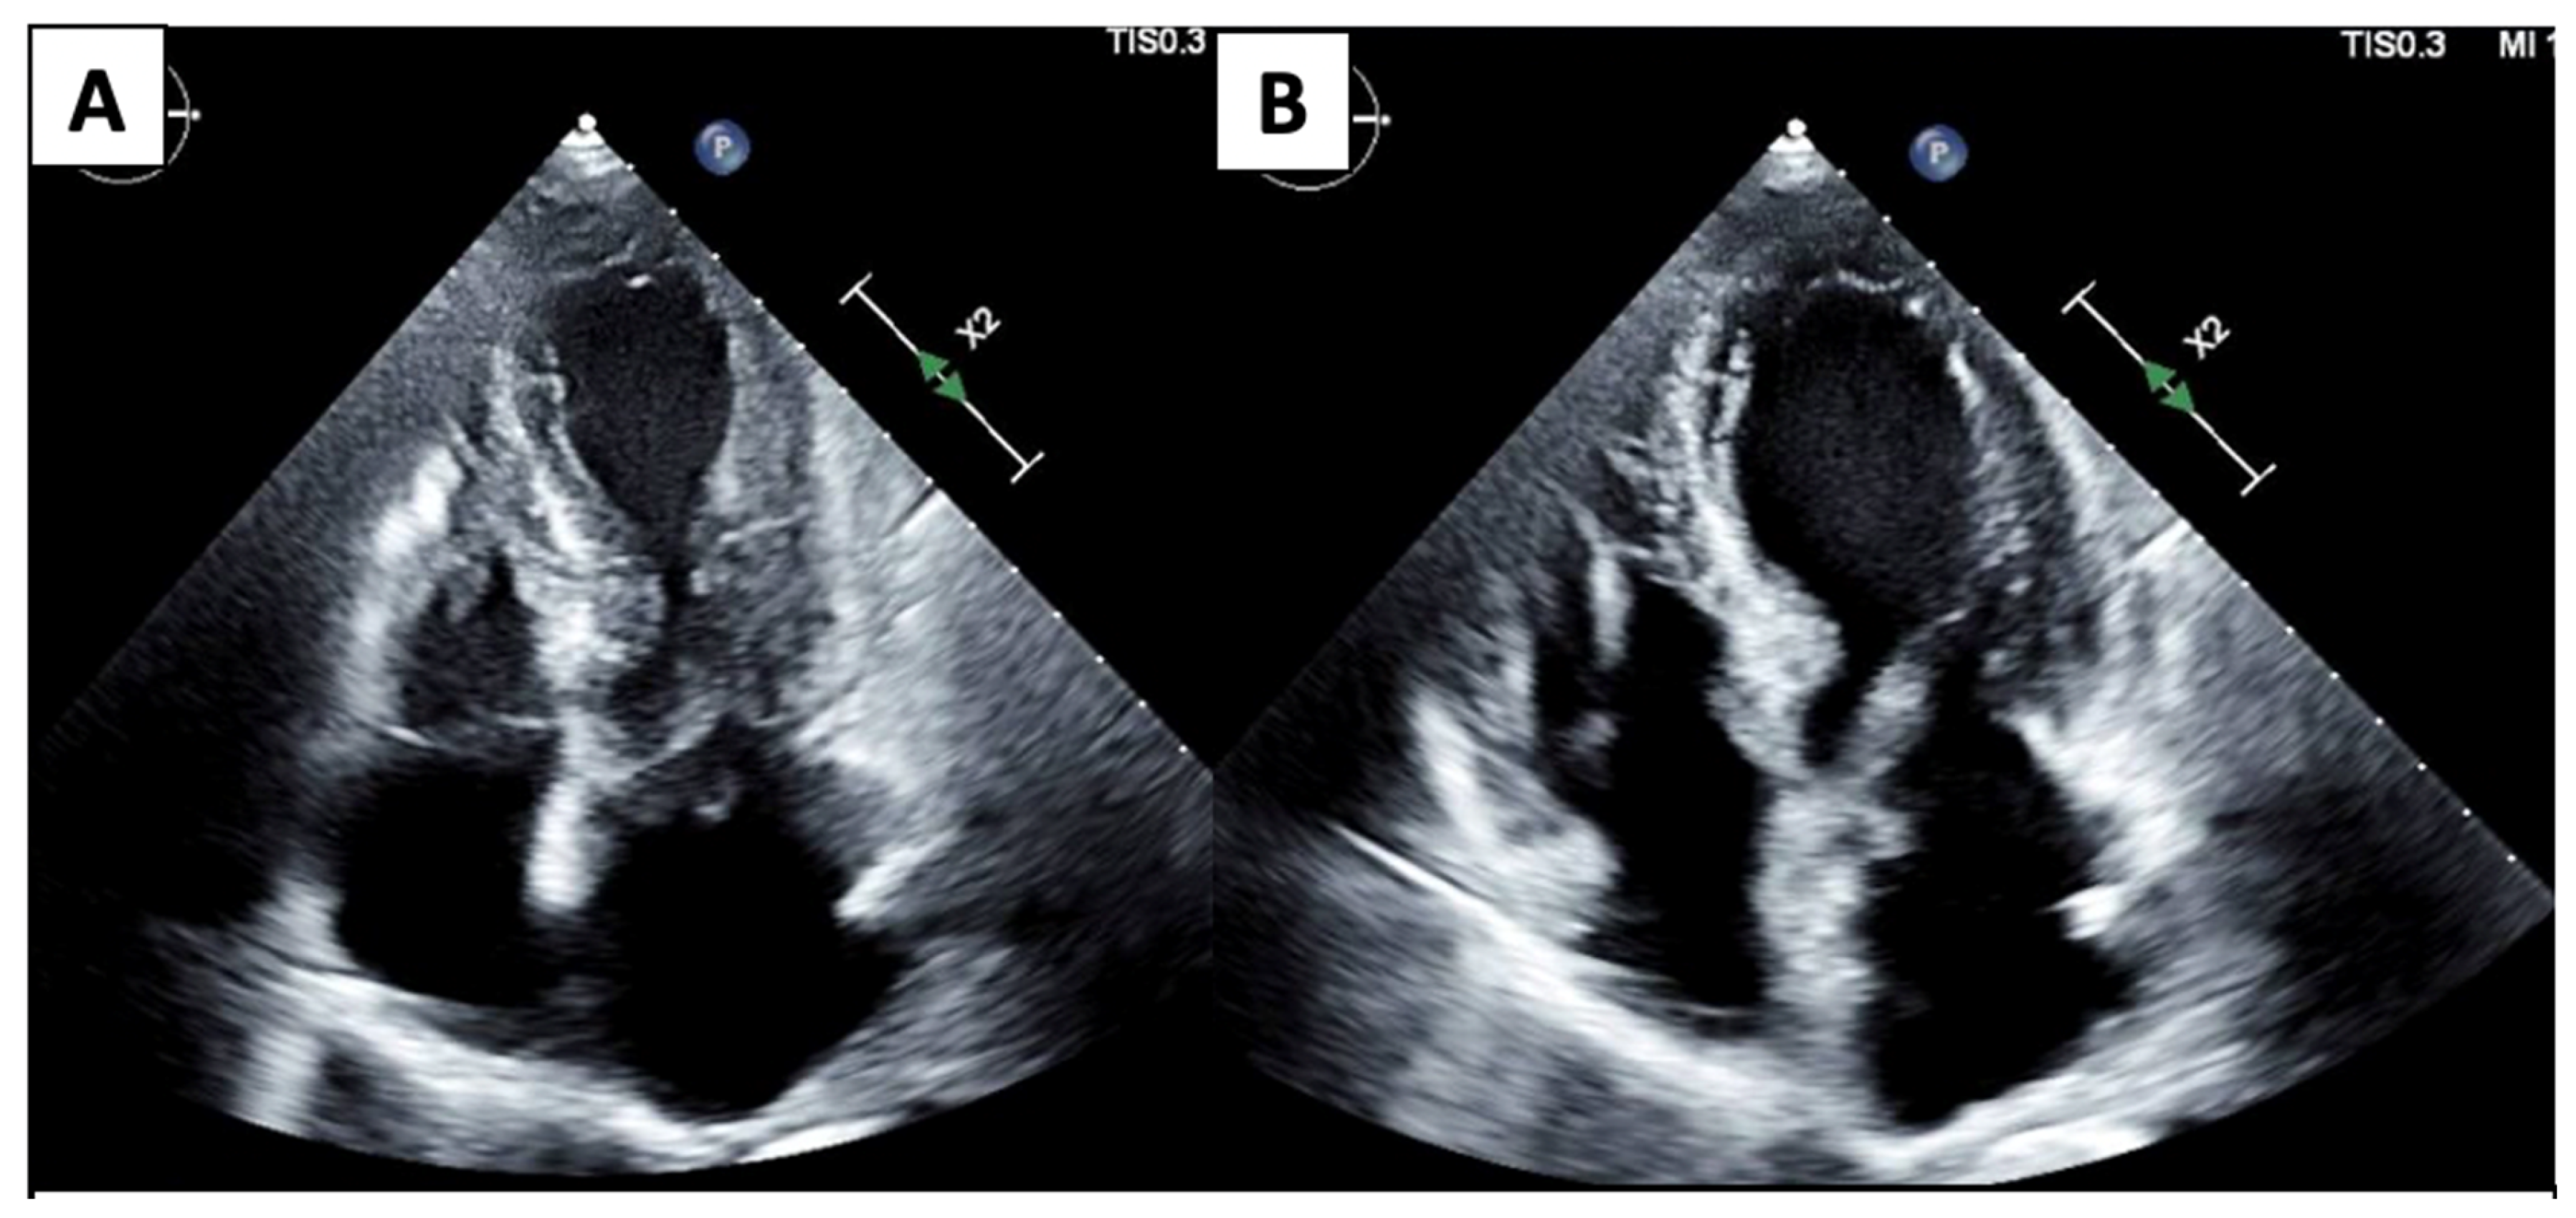

| Echocardiography | ![]() | Mild left-ventricular dilation and systolic dysfunction |